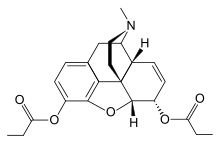

3,6-diesters of morphine

- Acetylpropionylmorphine

- 3,6-Dibutanoylmorphine

- Diacetyldihydromorphine (dihydroheroin, acetylmorphinol)

- Dibutyrylmorphine

- Dibenzoylmorphine (first designer drug)

- Diformylmorphine

- Dipropanoylmorphine

- Heroin (diacetylmorphine)

- Nicomorphine

Structures

| 3,6-diesters of morphine | ||||

|---|---|---|---|---|

Acetylpropionylmorphine Acetylpropionylmorphine |

3,6-Dibutanoylmorphine |  Diacetyldihydromorphine Diacetyldihydromorphine(dihydroheroin, acetylmorphinol) | ||

Dibutyrylmorphine Dibutyrylmorphine |

Dibenzoylmorphine Dibenzoylmorphine |

Diformylmorphine Diformylmorphine | ||

Dipropanoylmorphine Dipropanoylmorphine |

Heroin Heroin(diacetylmorphine) |

Nicomorphine Nicomorphine | ||